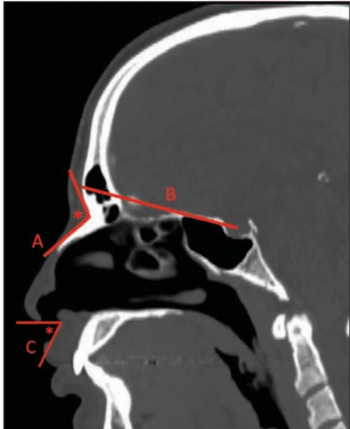

Using findings captured on CT scans, radiologists can improve the planning and outcomes for this surgery, improving the care of transgender women.